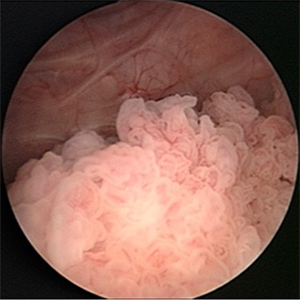

- Цистоскопия. Исследование при помощи специального эндоскопа, вводимого в мочевой пузырь, позволяет осмотреть его стенки изнутри и обнаружить патологическое изменение слизистой.

- Биопсия. Эндоскопическое исследование позволяет не только увидеть опухоль, но и изъять образец ткани для анализа.